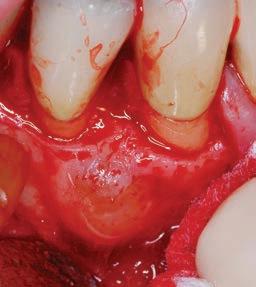

The third step of the treatment consisted of the crown lengthening, necessary to expose an adequate part of the root to obtain, after healing, the correct adhesion of the composite for the pre-prosthetic restoration and the successive prosthetic rehabilitation.

After the surgical flap elevation of the tissue and the bone remodeling, the flap was repositioned apically and sutured with a vertical mattress suture anchored in the periosteum (Figs. 5-6). The suture was removed after 7 days (Fig. 7).

glass fibre Figure 3: Root canal therapy completed under proper isolation. Figure 4: Radiography of completed root canal therapy and reconstruction made completely in glass hybrid cement. Figure 5: Clinical crown lengthening with a minimally invasive technique without mesial and distal discharges. Note the proximity of the reconstruction in glass hybrid material to the mesial bone ridge. Figure 6: Suture at the end of surgical therapy. It was left in place for 7 days Figure 7: Suture removal at 7 days. Post-surgical edema is still present.